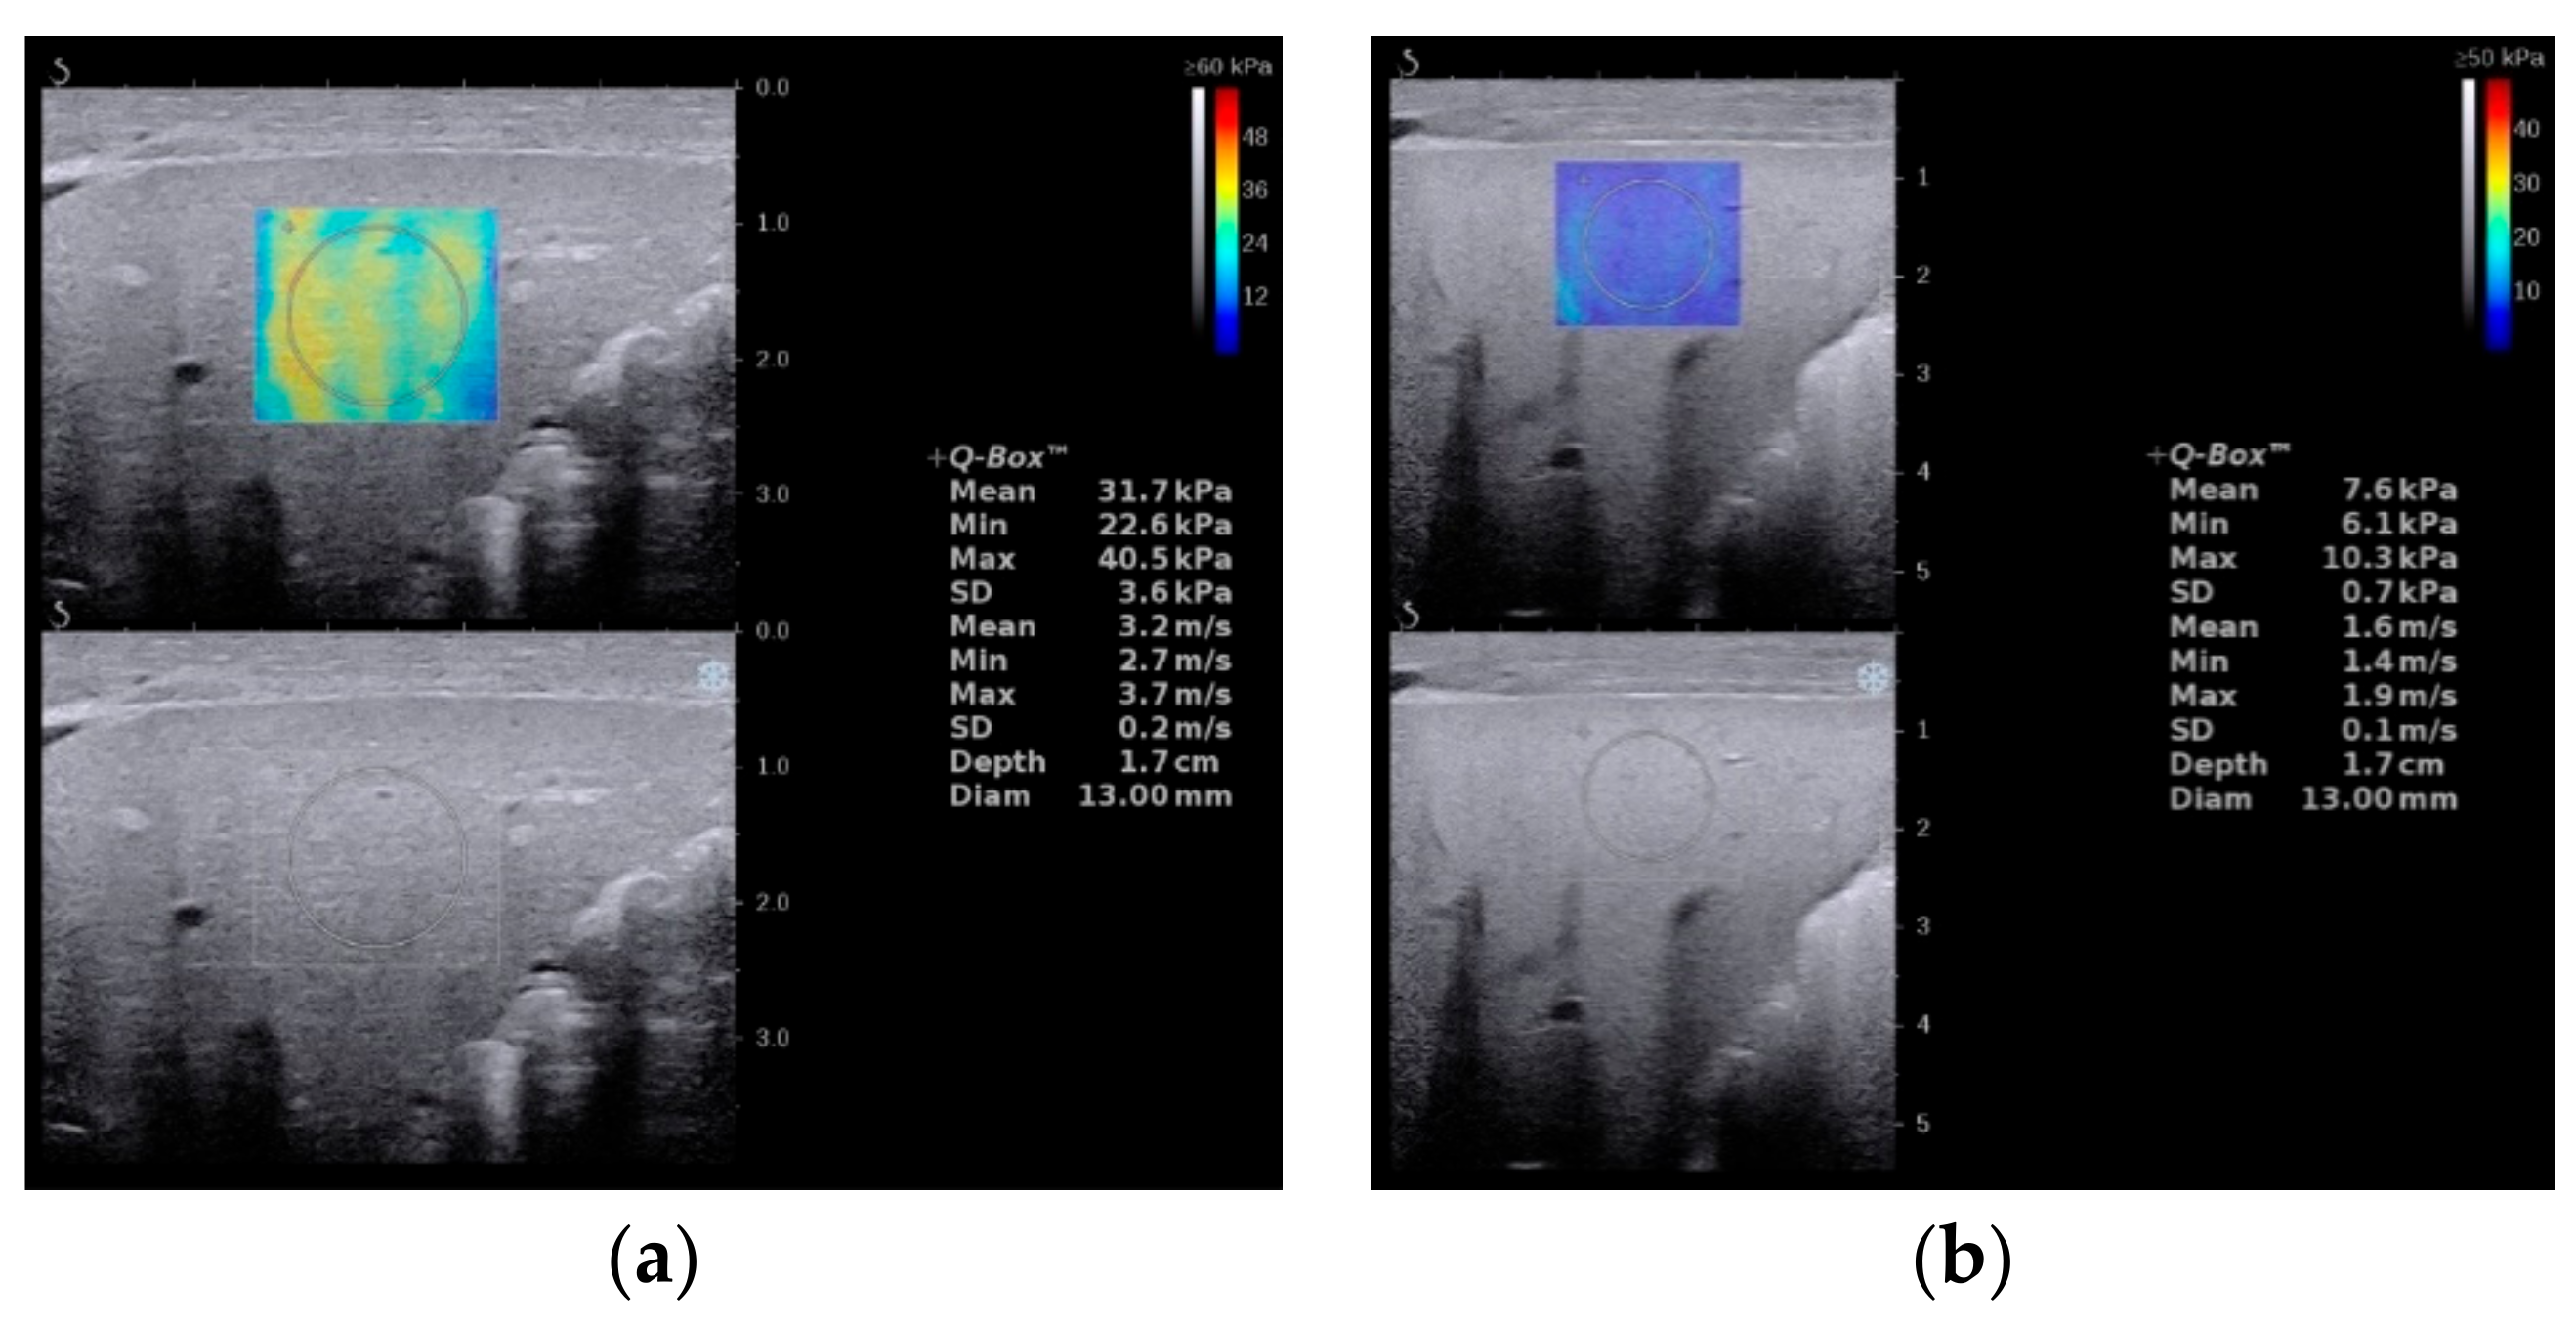

3. Elastography

- Zhou, L.-Y.; Jiang, H.; Shan, Q.-Y.; Chen, D.; Lin, X.-N.; Liu, B.-X.; Xie, X.-Y. Liver stiffness measurements with supersonic shear wave elastography in the diagnosis of biliary atresia: A comparative study with grey-scale US. Eur. Radiol. 2017, 27, 3474–3484. [Google Scholar] [CrossRef]

- Chen, H.; Zhou, L.; Liao, B.; Cao, Q.; Jiang, H.; Zhou, W.; Wang, G.; Xie, X. Two-Dimensional Shear Wave Elastography Predicts Liver Fibrosis in Jaundiced Infants with Suspected Biliary Atresia: A Prospective Study. Korean J. Radiol. 2021, 22, 959–969. [Google Scholar] [CrossRef]

- Galina, P.; Alexopoulou, E.; Mentessidou, A.; Mirilas, P.; Zellos, A.; Lykopoulou, L.; Patereli, A.; Salpasaranis, K.; Kelekis, N.L.; Zarifi, M. Diagnostic accuracy of two-dimensional shear wave elastography in detecting hepatic fibrosis in children with autoimmune hepatitis, biliary atresia and other chronic liver diseases. Pediatr. Radiol. 2021, 51, 1358–1368. [Google Scholar] [CrossRef]

- Gao, F.; Chen, Y.-Q.; Fang, J.; Gu, S.-L.; Li, L.; Wang, X.-Y. Acoustic Radiation Force Impulse Imaging for Assessing Liver Fibrosis Preoperatively in Infants with Biliary Atresia: Comparison with Liver Fibrosis Biopsy Pathology. J. Ultrasound Med. Off. J. Am. Inst. Ultrasound Med. 2017, 36, 1571–1578. [Google Scholar] [CrossRef]

- Wang, X.; Qian, L.; Jia, L.; Bellah, R.; Wang, N.; Xin, Y.; Liu, Q. Utility of Shear Wave Elastography for Differentiating Biliary Atresia from Infantile Hepatitis Syndrome. J. Ultrasound Med. Off. J. Am. Inst. Ultrasound Med. 2016, 35, 1475–1479. [Google Scholar] [CrossRef] [PubMed] [Green Version]

- Liu, Y.; Peng, C.; Wang, K.; Wu, D.; Yan, J.; Tu, W.; Chen, Y. The utility of shear wave elastography and serum biomarkers for diagnosing biliary atresia and predicting clinical outcomes. Eur. J. Pediatrics 2021, 30, 1–10. [Google Scholar] [CrossRef] [PubMed]

- Sandberg, J.K.; Sun, Y.; Ju, Z.; Liu, S.; Jiang, J.; Koci, M.; Rosenberg, J.; Rubesova, E.; Barth, R.A. Ultrasound shear wave elastography: Does it add value to gray-scale ultrasound imaging in differentiating biliary atresia from other causes of neonatal jaundice? Pediatr. Radiol. 2021, 51, 1654–1666. [Google Scholar] [CrossRef] [PubMed]

- Thumar, V.; Squires, J.H.; Spicer, P.J.; Robinson, A.L.; Chan, S.S. Ultrasound Elastography Applications in Pediatrics. Ultrasound Q. 2018, 34, 199–205. [Google Scholar] [CrossRef]

- Wu, J.-F.; Lee, C.-S.; Lin, W.-H.; Jeng, Y.-M.; Chen, H.-L.; Ni, Y.-H.; Hsu, H.-Y.; Chang, M.-H. Transient elastography is useful in diagnosing biliary atresia and predicting prognosis after hepatoportoenterostomy. Hepatology 2018, 68, 616–624. [Google Scholar] [CrossRef] [Green Version]

- Chen, S.; Liao, B.; Zhong, Z.; Zheng, Y.; Liu, B.; Shan, Q.; Xie, X.; Zhou, L. Supersonic shearwave elastography in the assessment of liver fibrosis for postoperative patients with biliary atresia. Sci. Rep. 2016, 6, 31057. [Google Scholar] [CrossRef]

- Leschied, J.R.; Dillman, J.R.; Bilhartz, J.; Heider, A.; Smith, E.A.; Lopez, M.J. Shear wave elastography helps differentiate biliary atresia from other neonatal/infantile liver diseases. Pediatr. Radiol. 2015, 45, 366–375. [Google Scholar] [CrossRef]

- Dillman, J.R.; DiPaola, F.W.; Smith, S.J.; Barth, R.A.; Asai, A.; Lam, S.; Campbell, K.M.; Bezerra, J.A.; Tiao, G.M.; Trout, A. Prospective Assessment of Ultrasound Shear Wave Elastography for Discriminating Biliary Atresia from other Causes of Neonatal Cholestasis. J. Pediatr. 2019, 212, 60–65.e3. [Google Scholar] [CrossRef]

- Hanquinet, S.; Courvoisier, D.S.; Rougemont, A.-L.; Dhouib, A.; Rubbia-Brandt, L.; Wildhaber, B.E.; Merlini, L.; McLin, V.A.; Anooshiravani, M. Contribution of acoustic radiation force impulse (ARFI) elastography to the ultrasound diagnosis of biliary atresia. Pediatr. Radiol. 2015, 45, 1489–1495. [Google Scholar] [CrossRef]

- Liu, Y.; Ni, X.; Pan, Y.; Luo, H. Comparison of the diagnostic value of virtual touch tissue quantification and virtual touch tissue imaging quantification in infants with biliary atresia. Int. J. Clin. Pr. 2021, 75, e13860. [Google Scholar] [CrossRef]

- Boo, Y.; Chang, M.; Jeng, Y.; Peng, S.; Hsu, W.; Lin, W.; Chen, H.; Ni, Y.; Hsu, H.; Wu, J. Diagnostic Performance of Transient Elastography in Biliary Atresia among Infants with Cholestasis. Hepatol. Commun. 2021, 5, 882–890. [Google Scholar] [CrossRef]

- Goldschmidt, I.; Streckenbach, C.; Dingemann, C.; Pfister, E.D.; di Nanni, A.; Zapf, A.; Baumann, U. Application and Limitations of Transient Liver Elastography in Children. J. Pediatr. Gastroenterol. Nutr. 2013, 57, 109–113. [Google Scholar] [CrossRef]

- Duan, X.; Peng, Y.; Liu, W.; Yang, L.; Zhang, J. Does Supersonic Shear Wave Elastography Help Differentiate Biliary Atresia from Other Causes of Cholestatic Hepatitis in Infants Less than 90 Days Old? Compared with Grey-Scale US. BioMed Res. Int. 2019, 2019, 9036362. [Google Scholar] [CrossRef] [Green Version]

- Wang, Y.; Jia, L.Q.; Hu, Y.X.; Xin, Y.; Yang, X.; Wang, X.M. Development and Validation of a Nomogram Incorporating Ultrasonic and Elastic Findings for the Preoperative Diagnosis of Biliary Atresia. Acad. Radiol. 2020, 28, S55–S63. [Google Scholar] [CrossRef]

- Chen, Y.; Zhao, D.; Gu, S.; Li, Y.; Pan, W.; Zhang, Y. Three-color risk stratification for improving the diagnostic accuracy for biliary atresia. Eur. Radiol. 2020, 30, 3852–3861. [Google Scholar] [CrossRef]

- Zhou, W.; Li, X.; Zhang, N.; Liao, B.; Xie, X.; Zhang, X.; Wang, G.; Zhou, L. The combination of conventional ultrasound and shear-wave elastography in evaluating the segmental heterogeneity of liver fibrosis in biliary atresia patients after Kasai portoenterostomy. Pediatr. Surg. Int. 2021, 37, 1099–1108. [Google Scholar] [CrossRef]

- Kim, J.R.; Suh, C.H.; Yoon, H.M.; Lee, J.S.; Cho, Y.A.; Jung, A.Y. The diagnostic performance of shear-wave elastography for liver fibrosis in children and adolescents: A systematic review and diagnostic meta-analysis. Eur. Radiol. 2018, 28, 1175–1186. [Google Scholar] [CrossRef]